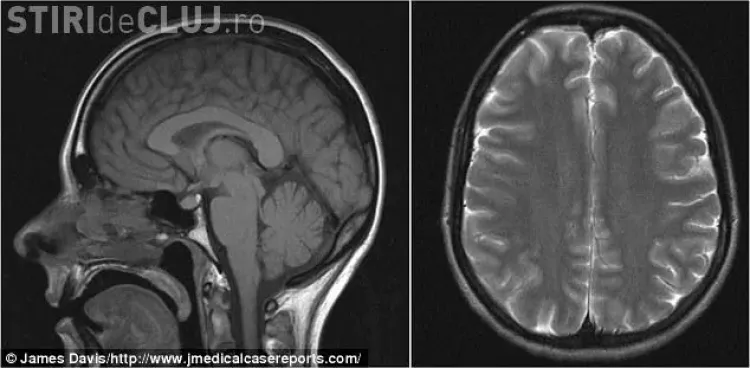

După ce i-au făcut un computer tomograf, medicii au stabilit că lichidul care se află în jurul creierului și a coloanei se scurgea printr-o ruptură musculară.